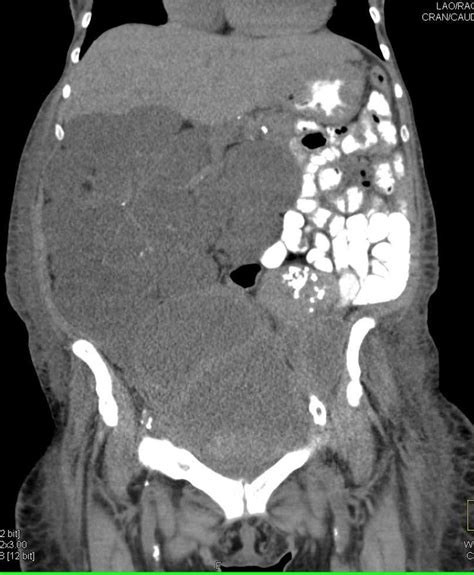

Alright, so we know PMP sounds serious, but how do you even spot it? The symptoms of Pseudomyxoma Peritonei (PMP) can be pretty vague, especially in the early stages. This is a big reason why diagnosis can sometimes take a while, guys. Because it grows slowly, people might just brush off symptoms as something less serious. Common signs include a feeling of fullness in your abdomen, gradual abdominal distension (your belly getting bigger over time), bloating, and sometimes discomfort or pain. You might notice changes in your bowel habits, like constipation or diarrhea, or even experience nausea and vomiting if the buildup becomes significant enough to press on your stomach or intestines. Unexplained weight gain, particularly around the abdomen, can also be a red flag. Some people might even notice a hernia that seems to be getting larger. It’s the gradual, persistent nature of these symptoms that should prompt a closer look. Diagnosing PMP usually involves a combination of medical history, physical examination, and imaging tests. Your doctor will likely ask detailed questions about your symptoms and any past medical history, especially related to the appendix or ovaries. Imaging is crucial here. CT scans are commonly used to visualize the abdominal cavity, detect the presence of mucin, and assess the extent of the disease, including any tumors or implants. MRI scans might also be used for better detail in certain areas. Ultrasound can sometimes pick up abnormalities, but CT scans are generally preferred for staging PMP. Blood tests might be done, but they usually don’t provide a definitive diagnosis for PMP itself; they can help check for signs of inflammation or other general health markers. The definitive diagnosis, however, often comes with a biopsy . This can be obtained during surgery or sometimes via a needle biopsy guided by imaging. Pathologists examine the tissue under a microscope to confirm the presence of mucinous adenocarcinoma and determine its origin. The characteristic accumulation of mucin and the specific cell types found in the biopsy are key diagnostic features of PMP. Sometimes, incidental findings during surgery for other conditions (like an appendectomy) can lead to an unexpected PMP diagnosis. For example, if an appendix is found to be distended with mucin during a routine appendectomy, further investigation for PMP is warranted. Early and accurate diagnosis is absolutely critical for PMP because it allows for timely intervention, which can significantly improve treatment outcomes and prognosis. The ability to distinguish PMP from other abdominal conditions that cause ascites is a testament to the advancements in diagnostic imaging and pathology. So, keep an ear out for those persistent, unexplained abdominal symptoms, guys, and don’t hesitate to get them checked out – it could be the key to catching PMP early. The journey from noticing a symptom to receiving a PMP diagnosis can be long, but with modern medical tools, it’s becoming more streamlined.